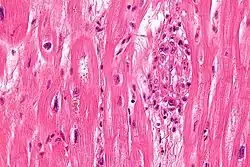

Micrograph showing an Aschoff body (right of image), as seen in rheumatic heart disease. H&E stain

S. pyogenes has a cell wall composed of branched polymers which sometimes contain M protein, a virulence factor that is highly antigenic. The antibodies which the immune system generates against the M protein may cross-react with heart muscle cell protein myosin,[15] heart muscle glycogen and smooth muscle cells of arteries, inducing cytokine release and tissue destruction. However, the only proven cross-reaction is with perivascular connective tissue. This inflammation occurs through direct attachment of complement and Fc receptor-mediated recruitment of neutrophils and macrophages. Characteristic Aschoff bodies, composed of swollen eosinophilic collagen surrounded by lymphocytes and macrophages, can be seen on light microscopy. The larger macrophages may become Anitschkow cells or Aschoff giant cells. Rheumatic valvular lesions may also involve a cell-mediated immunity reaction as these lesions predominantly contain T-helper cells and macrophages.[16]